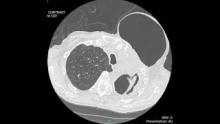

The patient is a sixty-seven-year-old man diagnosed with stage IIIA moderately differentiated squamous cell carcinoma of the left upper lobe. He completed neoadjuvant chemoradiation and underwent a left thoracotomy, left upper lobectomy, and mediastinal lymph node dissection. His course was complicated by necrotizing pneumonia and chronic empyema. He required prolonged drainage with an indwelling chest tube, decortication, and coverage of the left apical cavity with a pectoralis muscle flap. After removal of the chest tube, he developed a bronchocutaneous fistula and subsequent pneumothorax necessitans of the left anterior chest wall.

The patient underwent percutaneous placement of an 8 French pigtail catheter into the anterior chest wall subcutaneous air collection. A flexible bronchoscopy demonstrated an intact left upper lobe bronchial stump. The balloon of a 4mm Fogarty catheter was used to isolate the air leak to the superior segment of the left lower lobe. The subcutaneous air collection resolved. After deflating the Fogarty catheter balloon, the subcutaneous air collection reaccumulated. A 6mm endobronchial valve was deployed into the superior segment bronchi, and the pigtail catheter was clamped. There was no reaccumulation of the anterior chest wall subcutaneous air collection, and the pigtail catheter was removed the next day.

Six weeks later, the patient underwent a flexible bronchoscopy and removal of the endobronchial valve. The subcutaneous air collection did not recur, and the bronchocutaneous fistula and pneumothorax necessitans resolved.